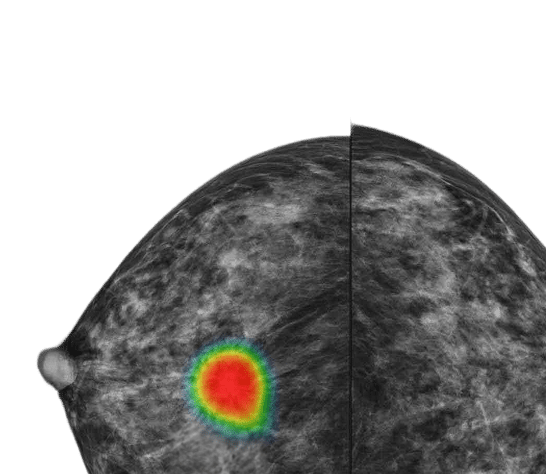

기존 워크플로우에 자연스럽게 통합되는 루닛 인사이트는 암 진단을 보조합니다. 연결된 에코시스템을 기반으로 판독 효율을 높이고, 의료진의 판단을 돕도록 설계됐습니다.